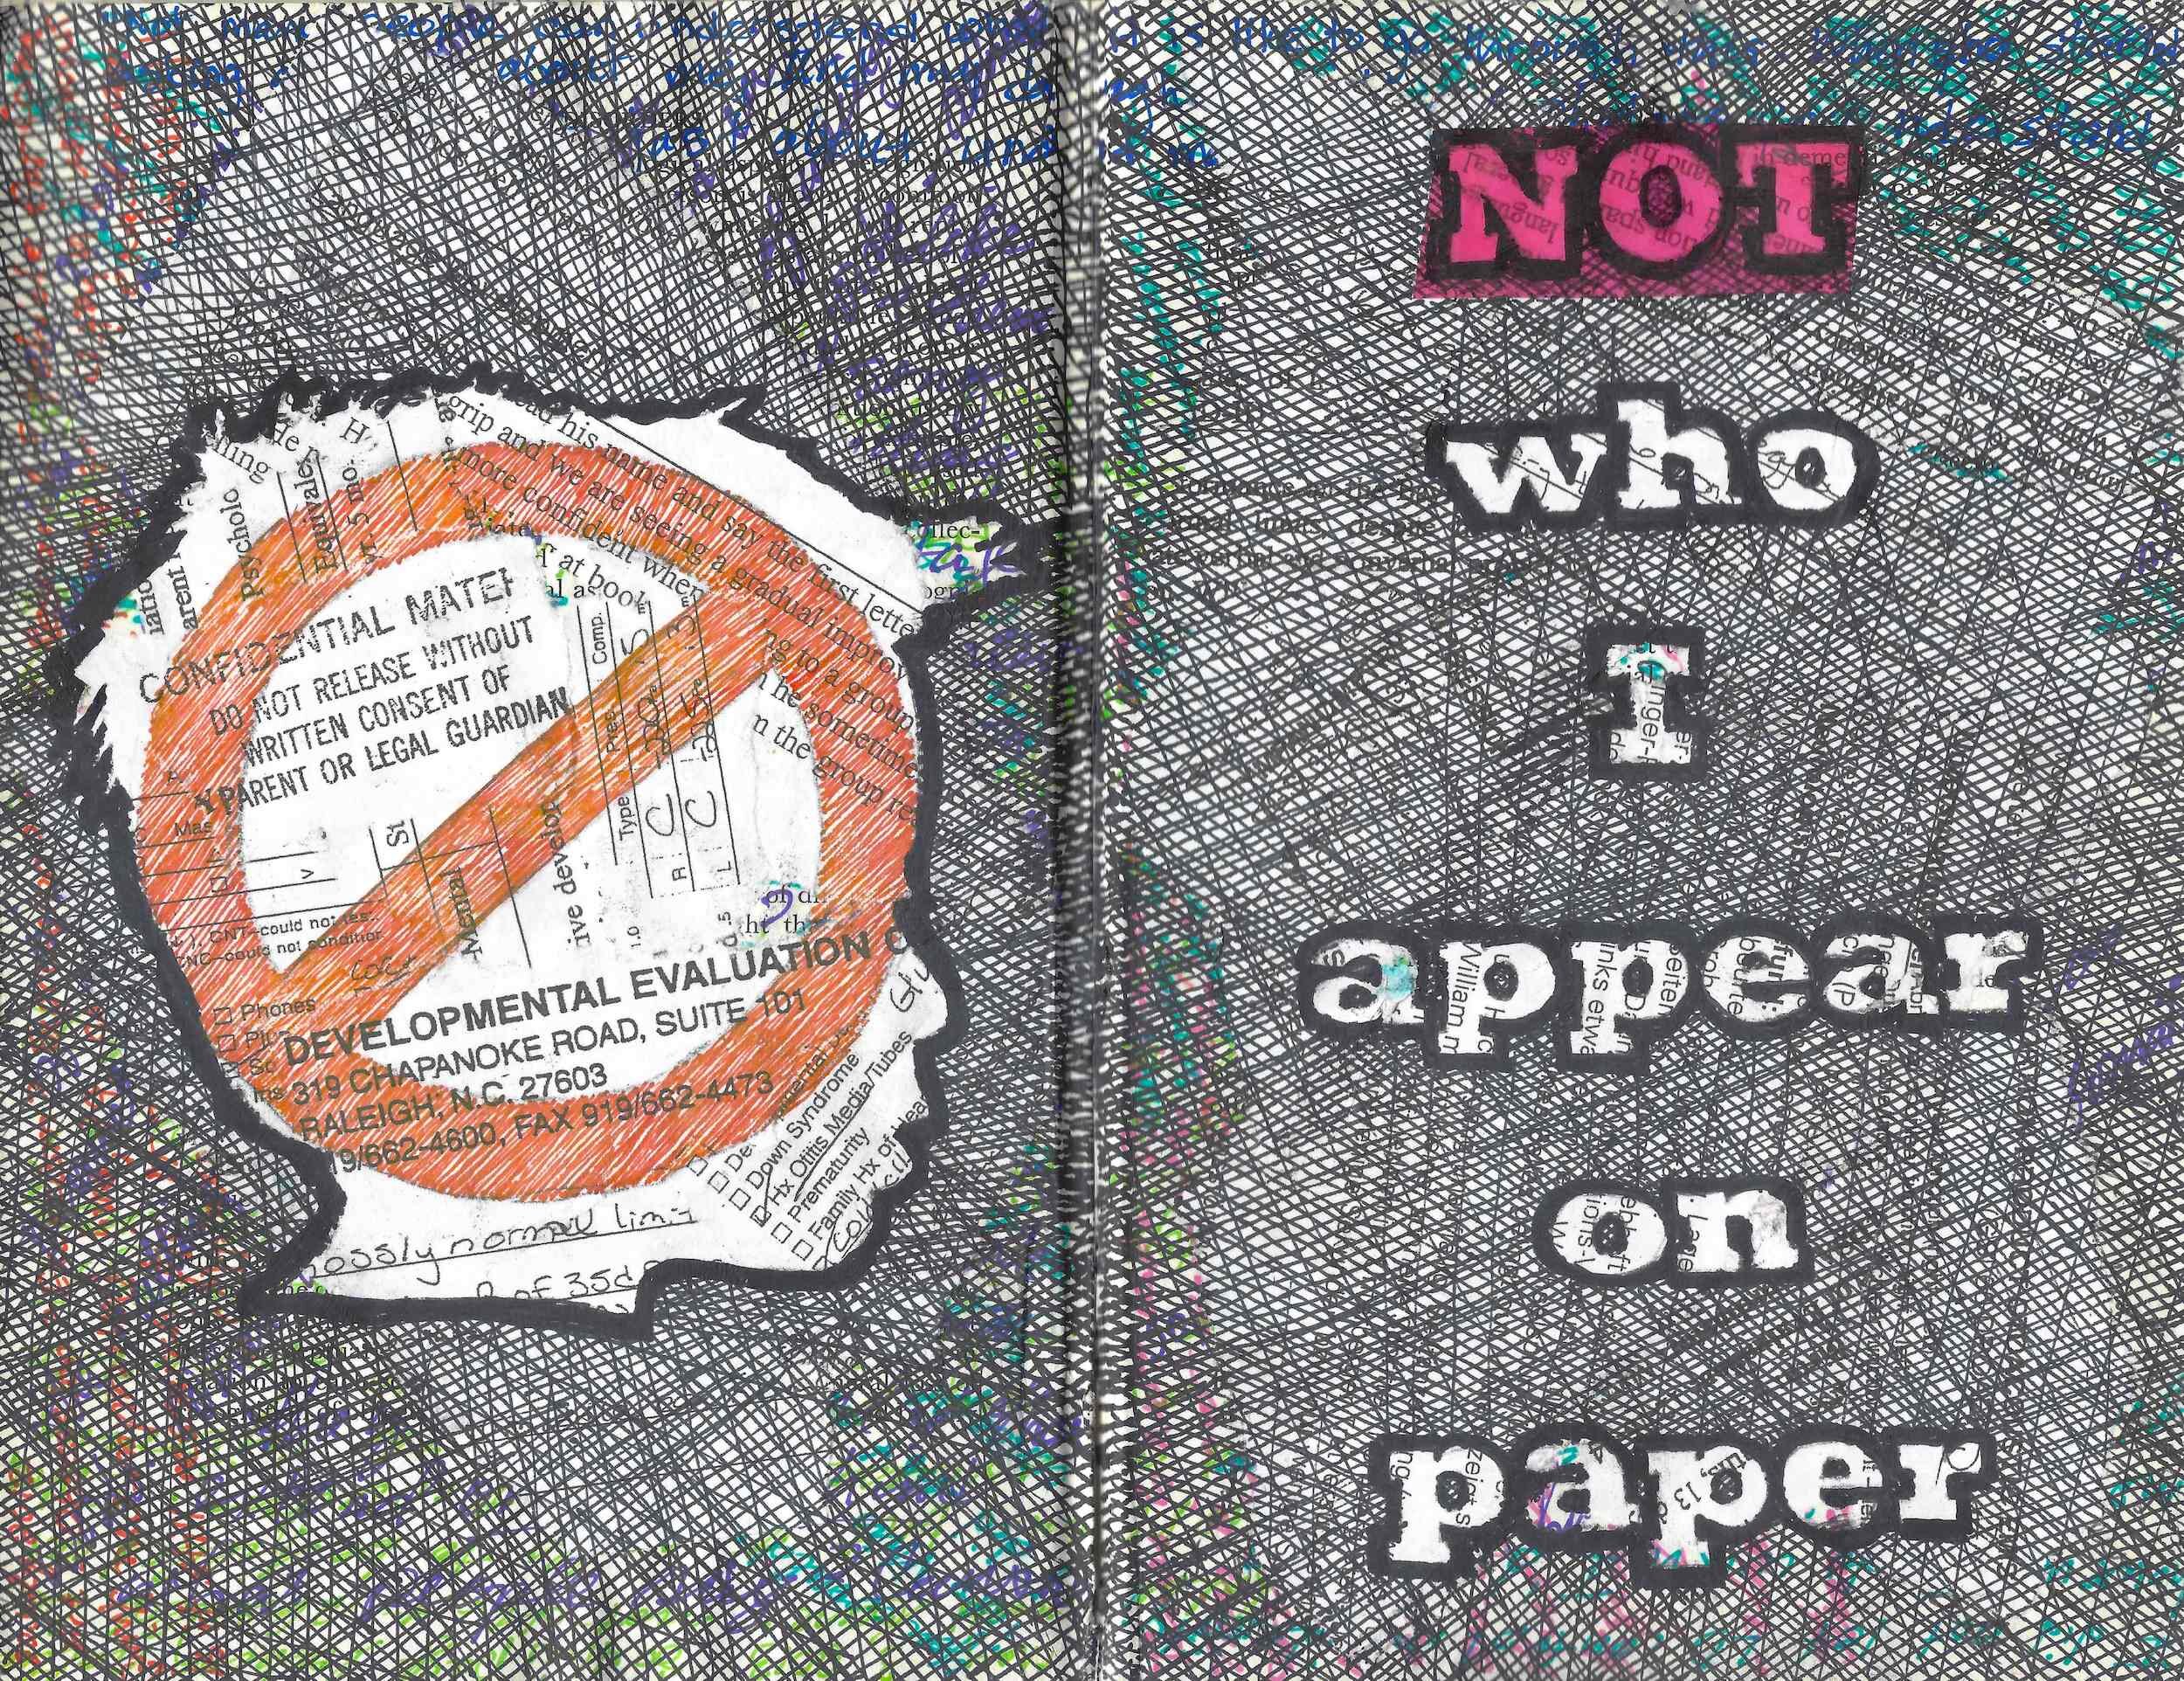

Re/Claimed is a part of an on-going quest to re/present experiences of learning disability for myself and others like me in non-standard ways. In this instance, journaling, stripping, and altering pages of a venerated 1961 learning disorders textbook results in original works of art that juxtapose old knowledges with fresh perceptions. The intention is to challenge mainstream stereotypes of learning disability by opening opportunities for us to be seen, understood, and known as embodied, multidimensional beings with unique sets of abilities.

Not Who I Appear On Paper